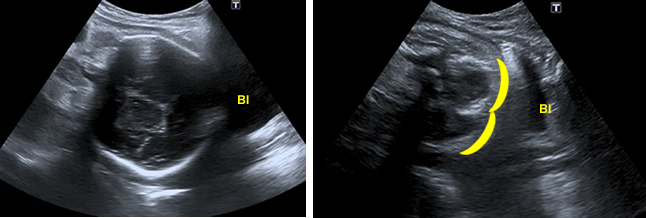

The lie or presentation of the baby is particularly important in late pregnancy, as the baby is less likely to change position. At this stage, certain critical features of the head and rump should allow you identify the presentation.

The fetal head is an oval structure. The bones of the skull produce bright echoes.

In the left image, you can see the bones of the skull of the fetus in the lower part of the uterus next to the bladder (bl). In the right image, the baby is in breech presentation. You can see the outline of the baby’s bottom next to the maternal bladder (bl).